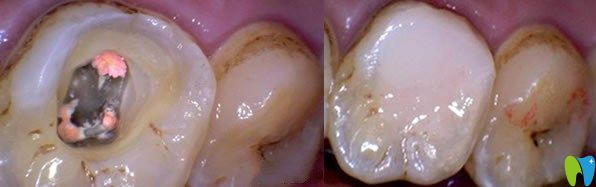

一、急性牙髓炎如何治療?

急性牙髓炎主要是細(xì)菌感染引起牙髓組織的急性炎癥,遇冷更加疼痛。急性牙髓炎發(fā)病急,疼痛劇烈,牙齦紅腫、化膿等癥狀,一般鎮(zhèn)痛藥物效果不明顯,遇到良心牙醫(yī)會(huì)保存活髓及患牙,利用開髓及藥物來(lái)緩解疼痛,服用消炎藥兩到三天,疼痛緩解后,嚴(yán)重的牙髓炎可采取根管治療或者活髓切斷術(shù),能夠及時(shí)預(yù)防病情嚴(yán)重及擴(kuò)散。沒有保存價(jià)值的牙齒可拔掉。

急性牙髓炎治療方法